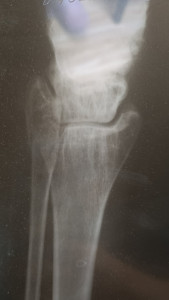

Здравствуйте. Добавила более ясное фото.. Такой снимок на рентгене. У меня перелом, а вот чего именно врач не сказал. Кости или самой лодыжки? Наложили гипс, но он очень стал давить. Пришла на прием к травматологу и его сняли с болью, просто ужас. И

отправили домой, вообще без ничего. Сказали купите ортез и носите. Оденете дома. Я на костылях пропрыгала почти 2 суток в эластичном бинте. Скажите пожалуйста, снятие гипса не может повлечь за собой дальнейшее смещение и перелом именно какой части у меня? Спасибо

Здравствуйте. На снимках виден перелом в области лодыжки, предположительно дистального отдела малоберцовой кости. Снимок с красным пятном не информативен для оценки. Снятие гипса при нестабильных переломах может привести к смещению, поэтому ортез нужно носить постоянно, а контрольный рентген обязателен. Рекомендую как можно скорее повторно обратиться к травматологу для уточнения стабильности перелома и правильной фиксации.